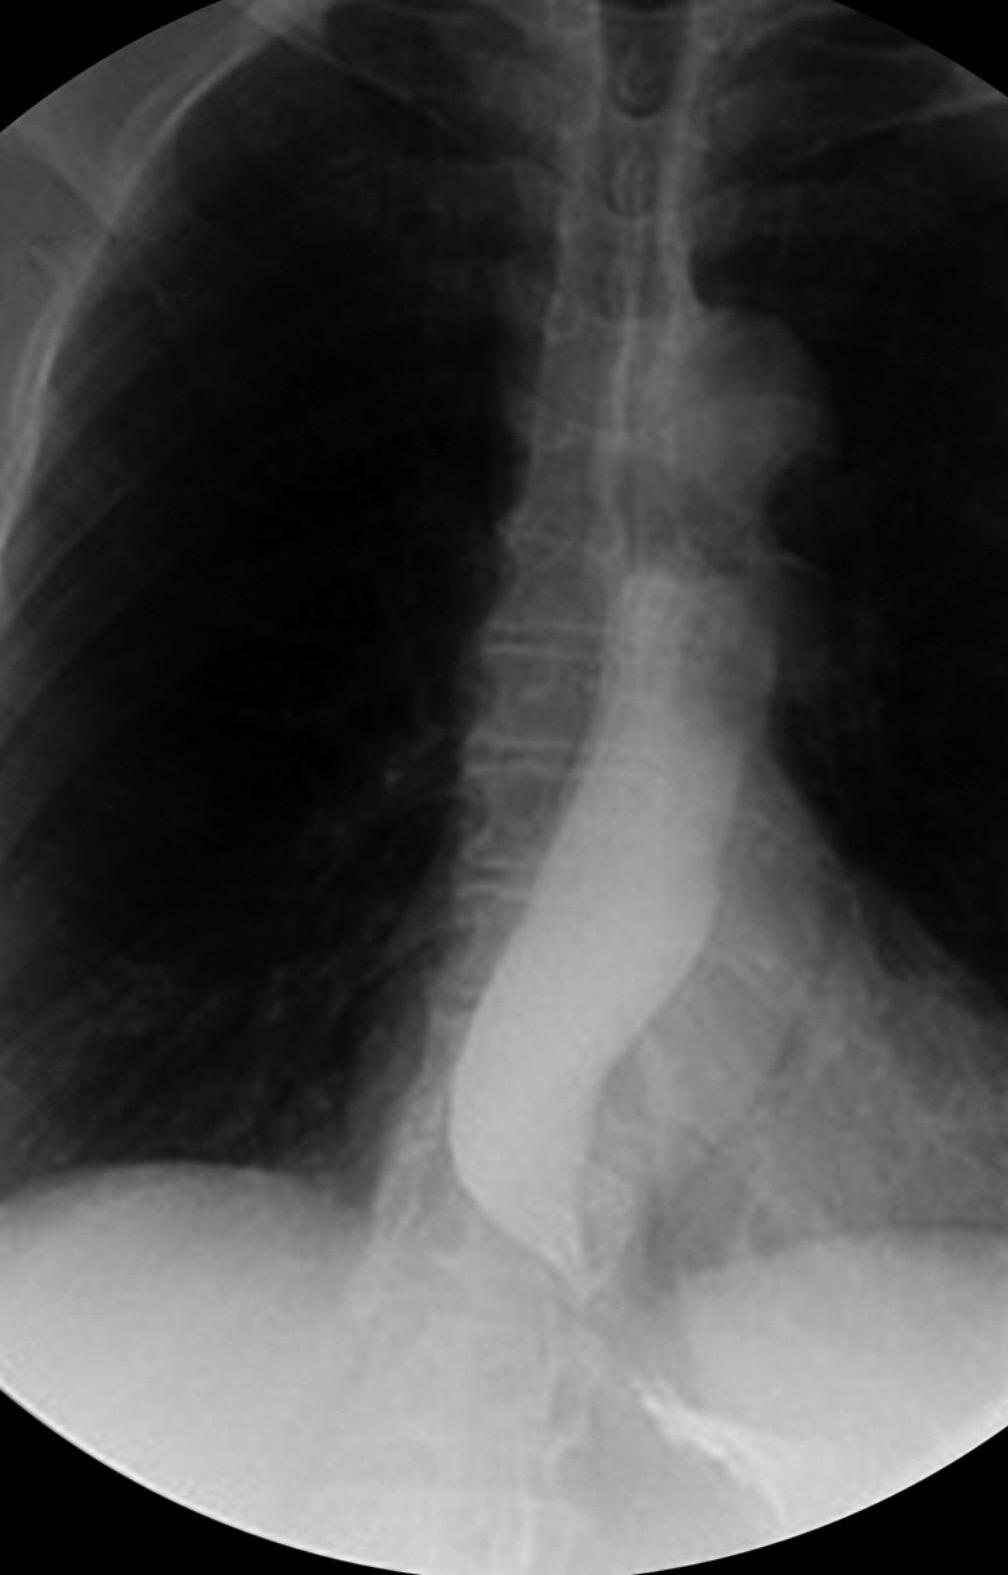

Figura 7.1 (A a C) Radiografia contrastada de esôfago demonstrando . Junção esofagogástrica sem relaxamento e afilada com aspecto de bico de pássaro (seta) (A) Esôfago dilatado com estase do contraste formando nível hidroaéreo (seta) (B) . Esôfago “sigmoidizado” (dilatado e tortuoso) com resíduos alimentares (seta demonstrando áreas escuras compatíveis com resíduos alimentares em meio ao contraste branco) (C)

Fonte: imagens dos autores